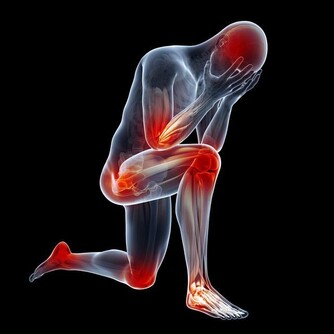

那麼缺乏這類微量元素為什麼會造成如此嚴重的後果呢?

這是因為氧化應激與細胞癌變息息相關,

人體缺硒時無法阻攔氧化應激對細胞帶來的損傷,進而會增加罹患癌症的風險。